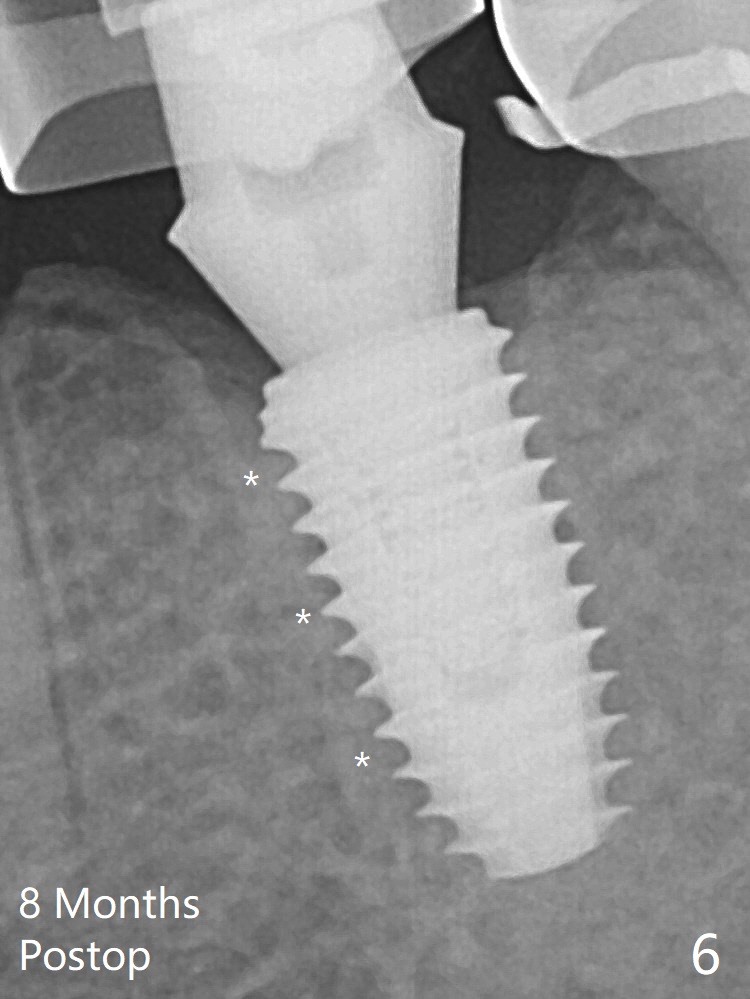

A 5x10 mm implant is intentionally placed distal at #19 using guided surgery (Fig.1). When it is osteointegrated, it will be used as an anchorage to upright the tooth #18 orthodontically. In fact the implant is mistakenly placed 1.5 mm deeper than planned without significant side effect (paresthesia). The healing abutment dislodges (probably as related to deep placement of the implant) 20 days postop and is retightened. There is mild crestal bone loss 4 months postop (Fig.2). The tooth #18 is distalized ~ 1 mm shown by X-ray, although more clinically, 2.5 months post open coil spring. The bone density around the implant, particularly mesial (Fig.6 *), increases 8 months postop, as compared to Fig.2. Distal Placement Last Next Xin Wei, DDS, PhD, MS 1st edition 01/05/2019, last revision 02/23/2019